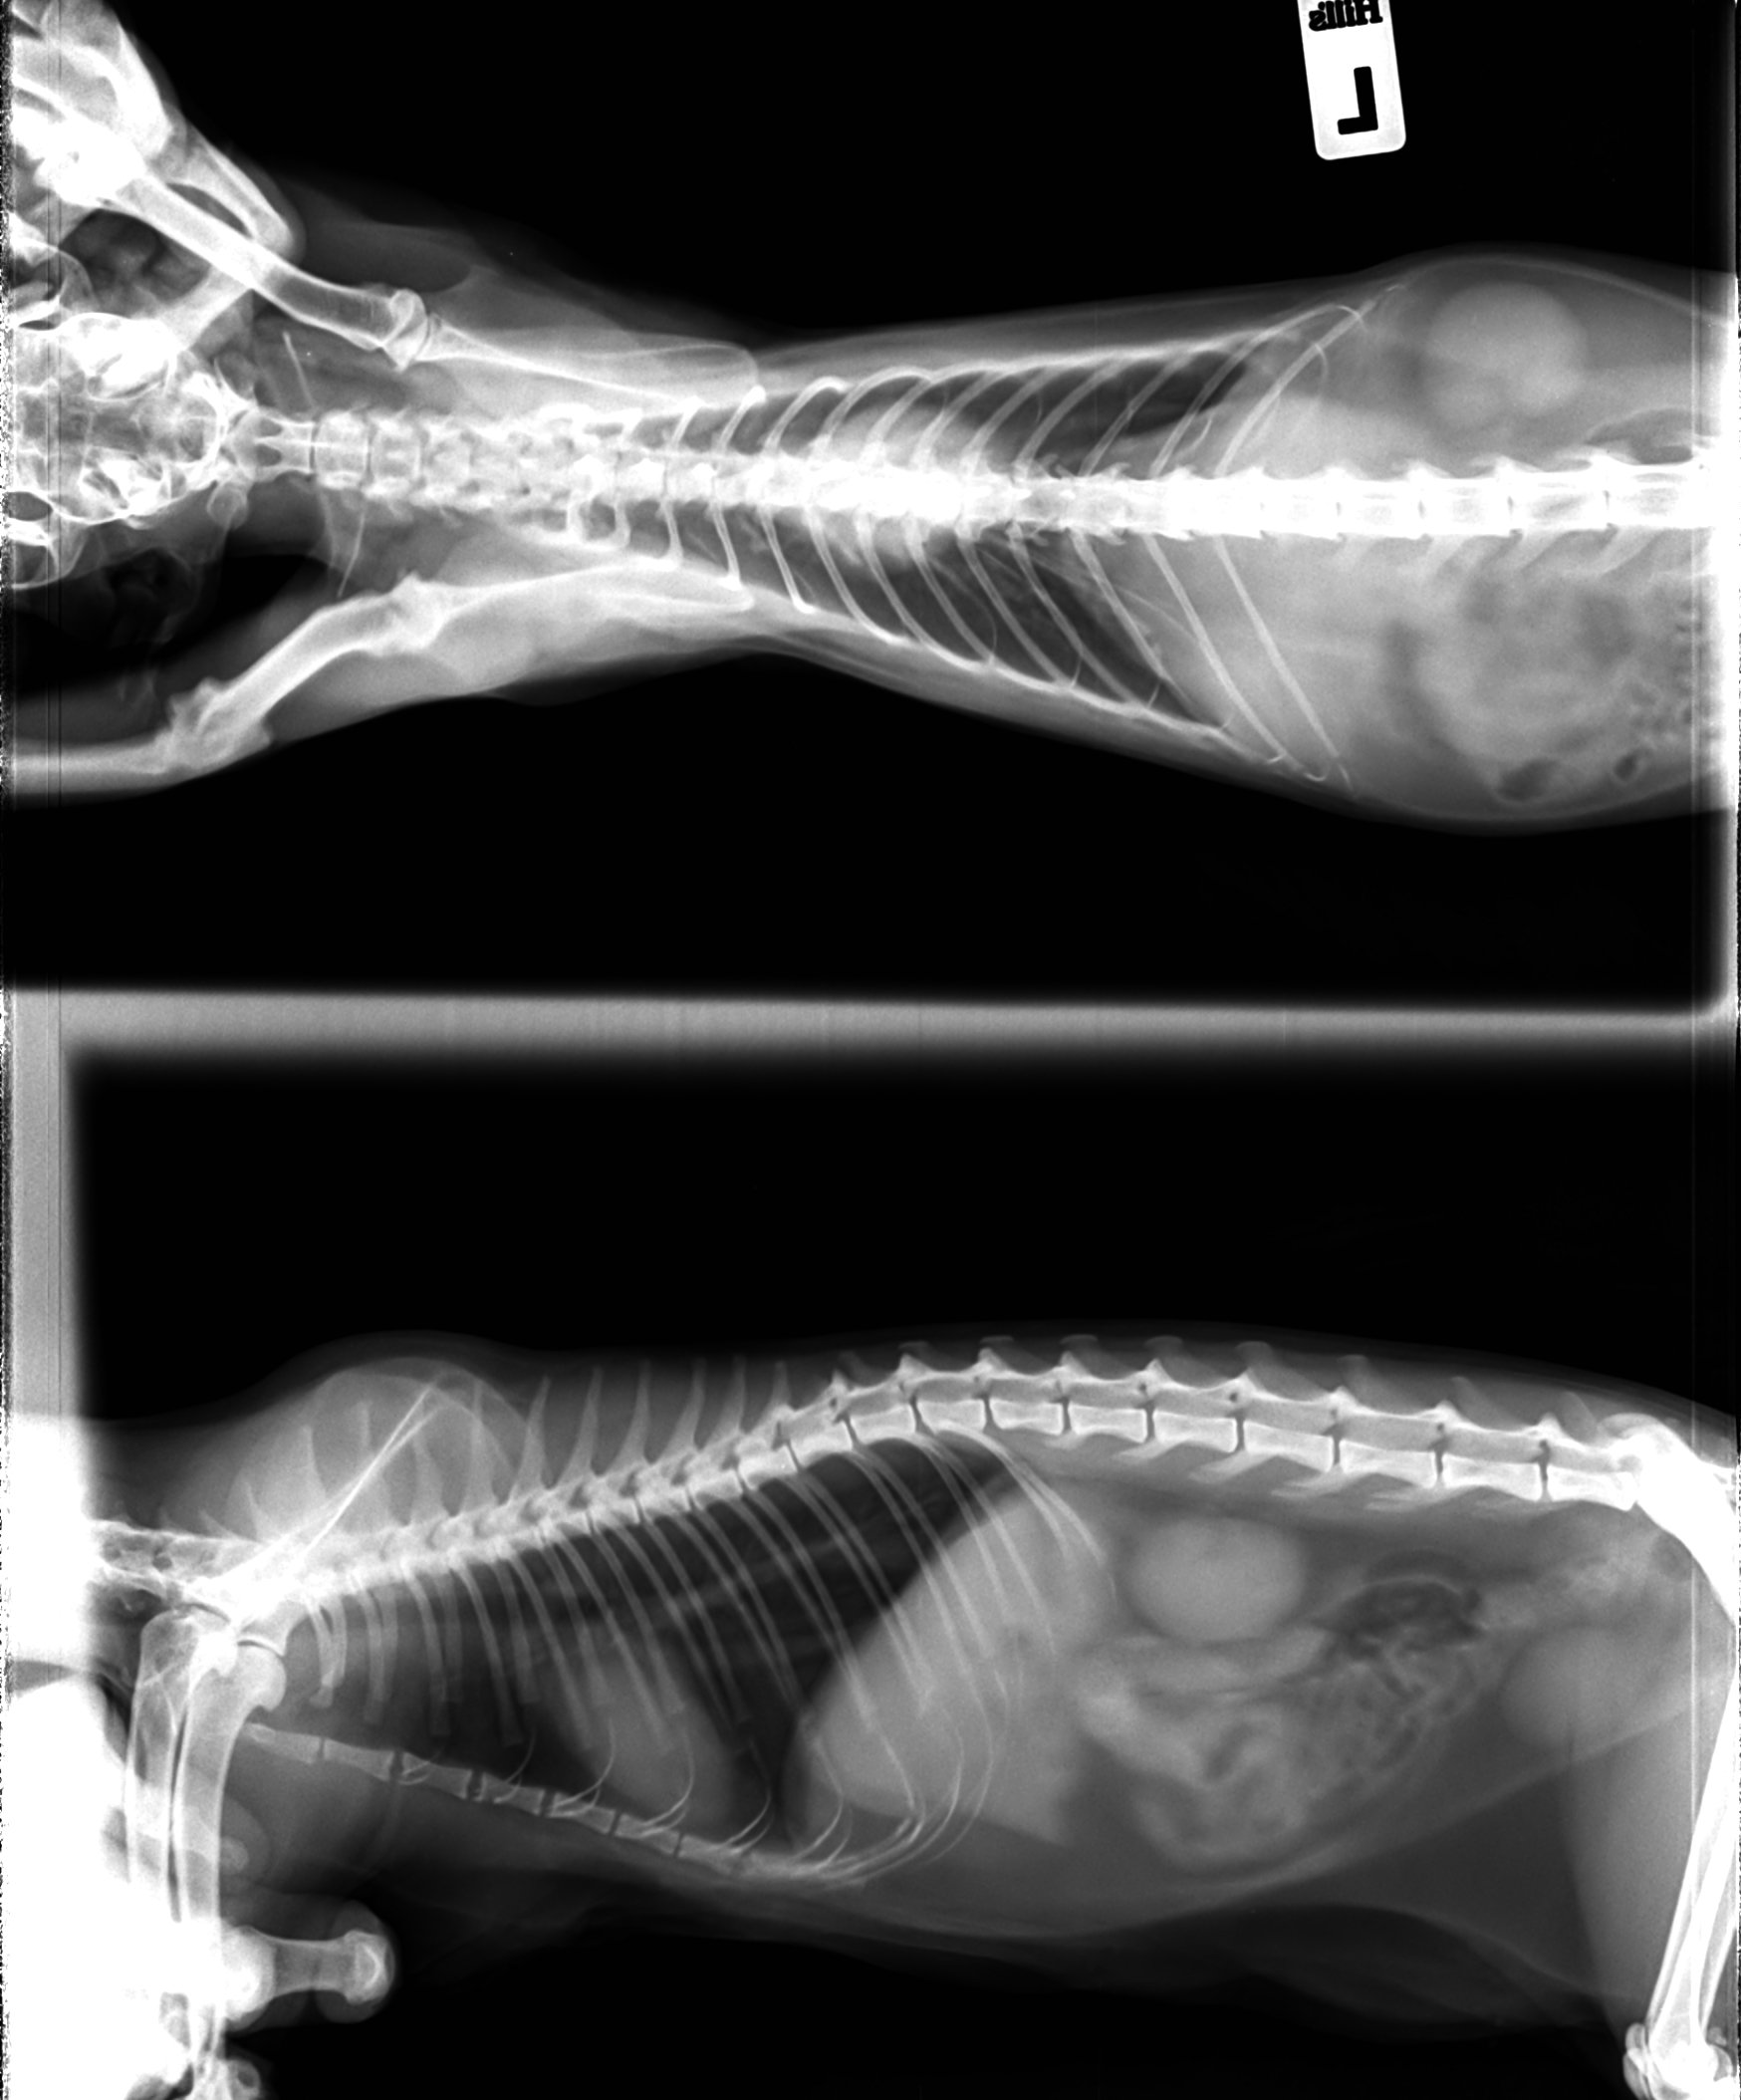

Рентгенологическая диагностика саркомы у кошек

Раздел: Визуальный дайджест